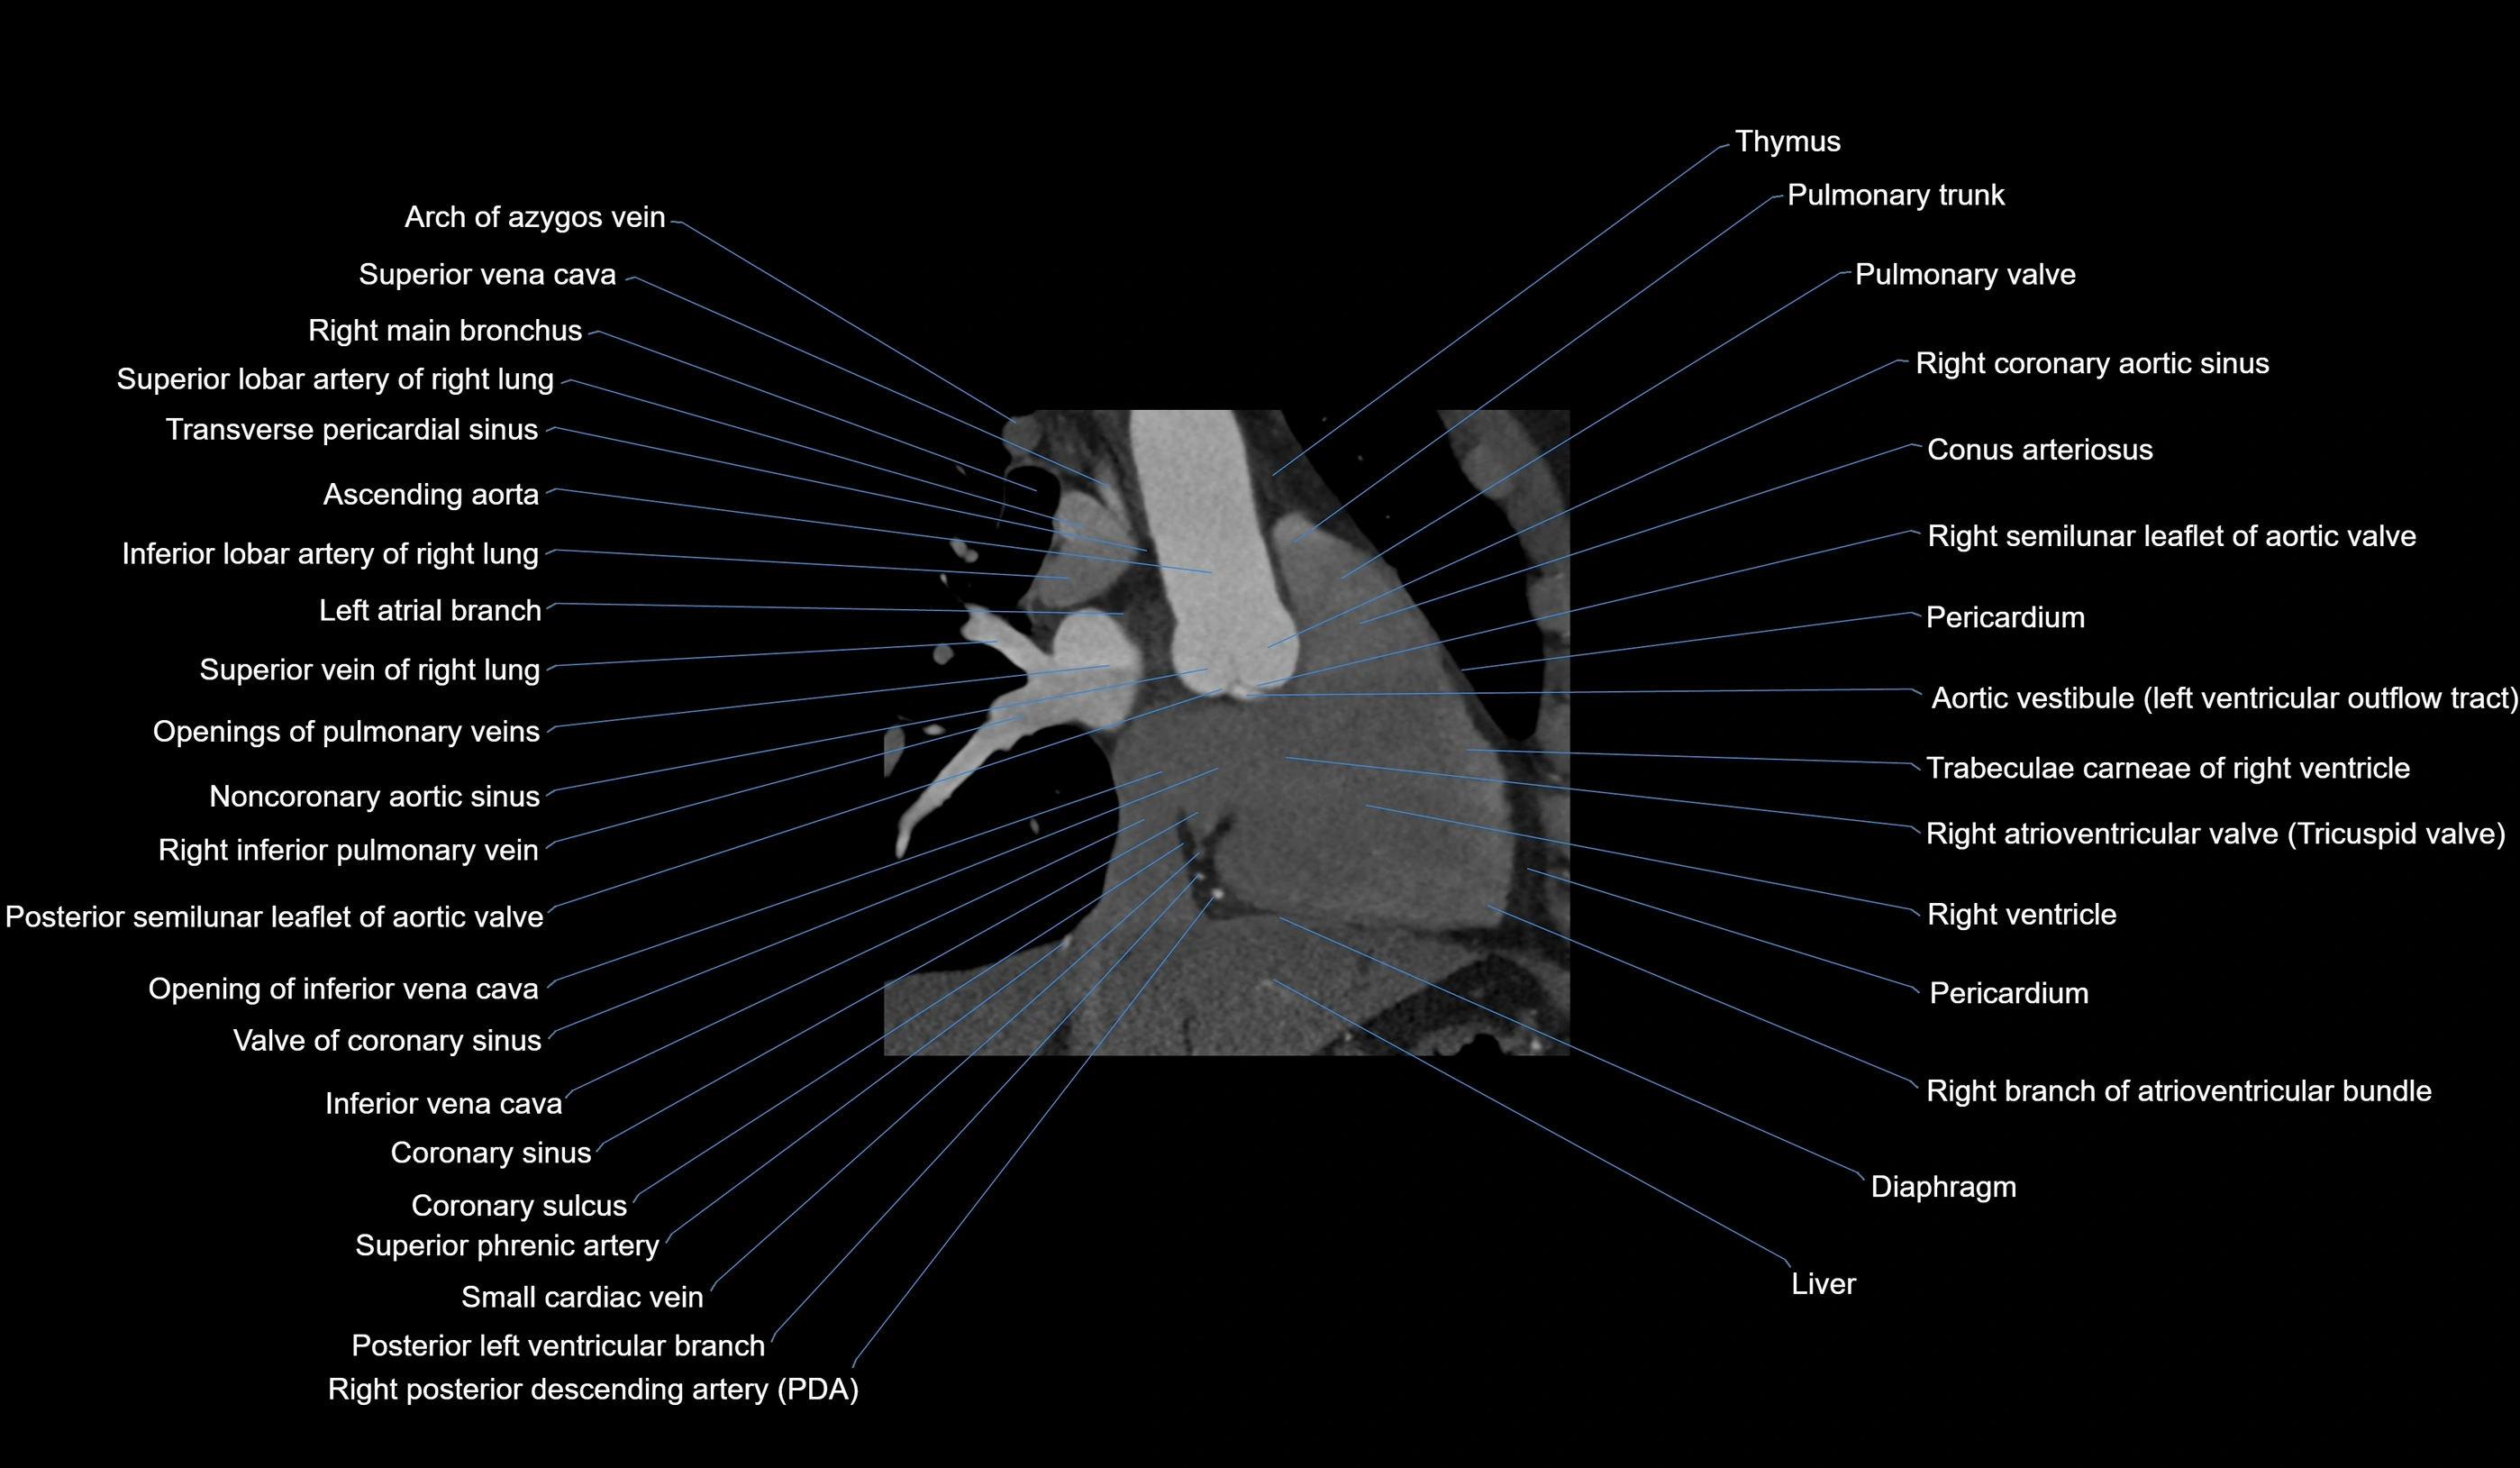

CT Appearance

Non-contrast CT (Calcium Scoring):

-

AM artery visualized for coronary calcium scoring

Calcified plaques appear as hyperdense foci; scored with Agatston method

CT Coronary Angiography (CCTA):

Best non-invasive modality for acute marginal artery visualization

Shows origin, course along the acute margin, and right ventricular branches

Detects stenosis, occlusion, calcified and non-calcified plaques, aneurysm, or anomalous course

Multiplanar reformats and 3D reconstructions help in pre-PCI and surgical planning

Critical for assessing right ventricular infarction risk in RCA disease

MRI image

CT images